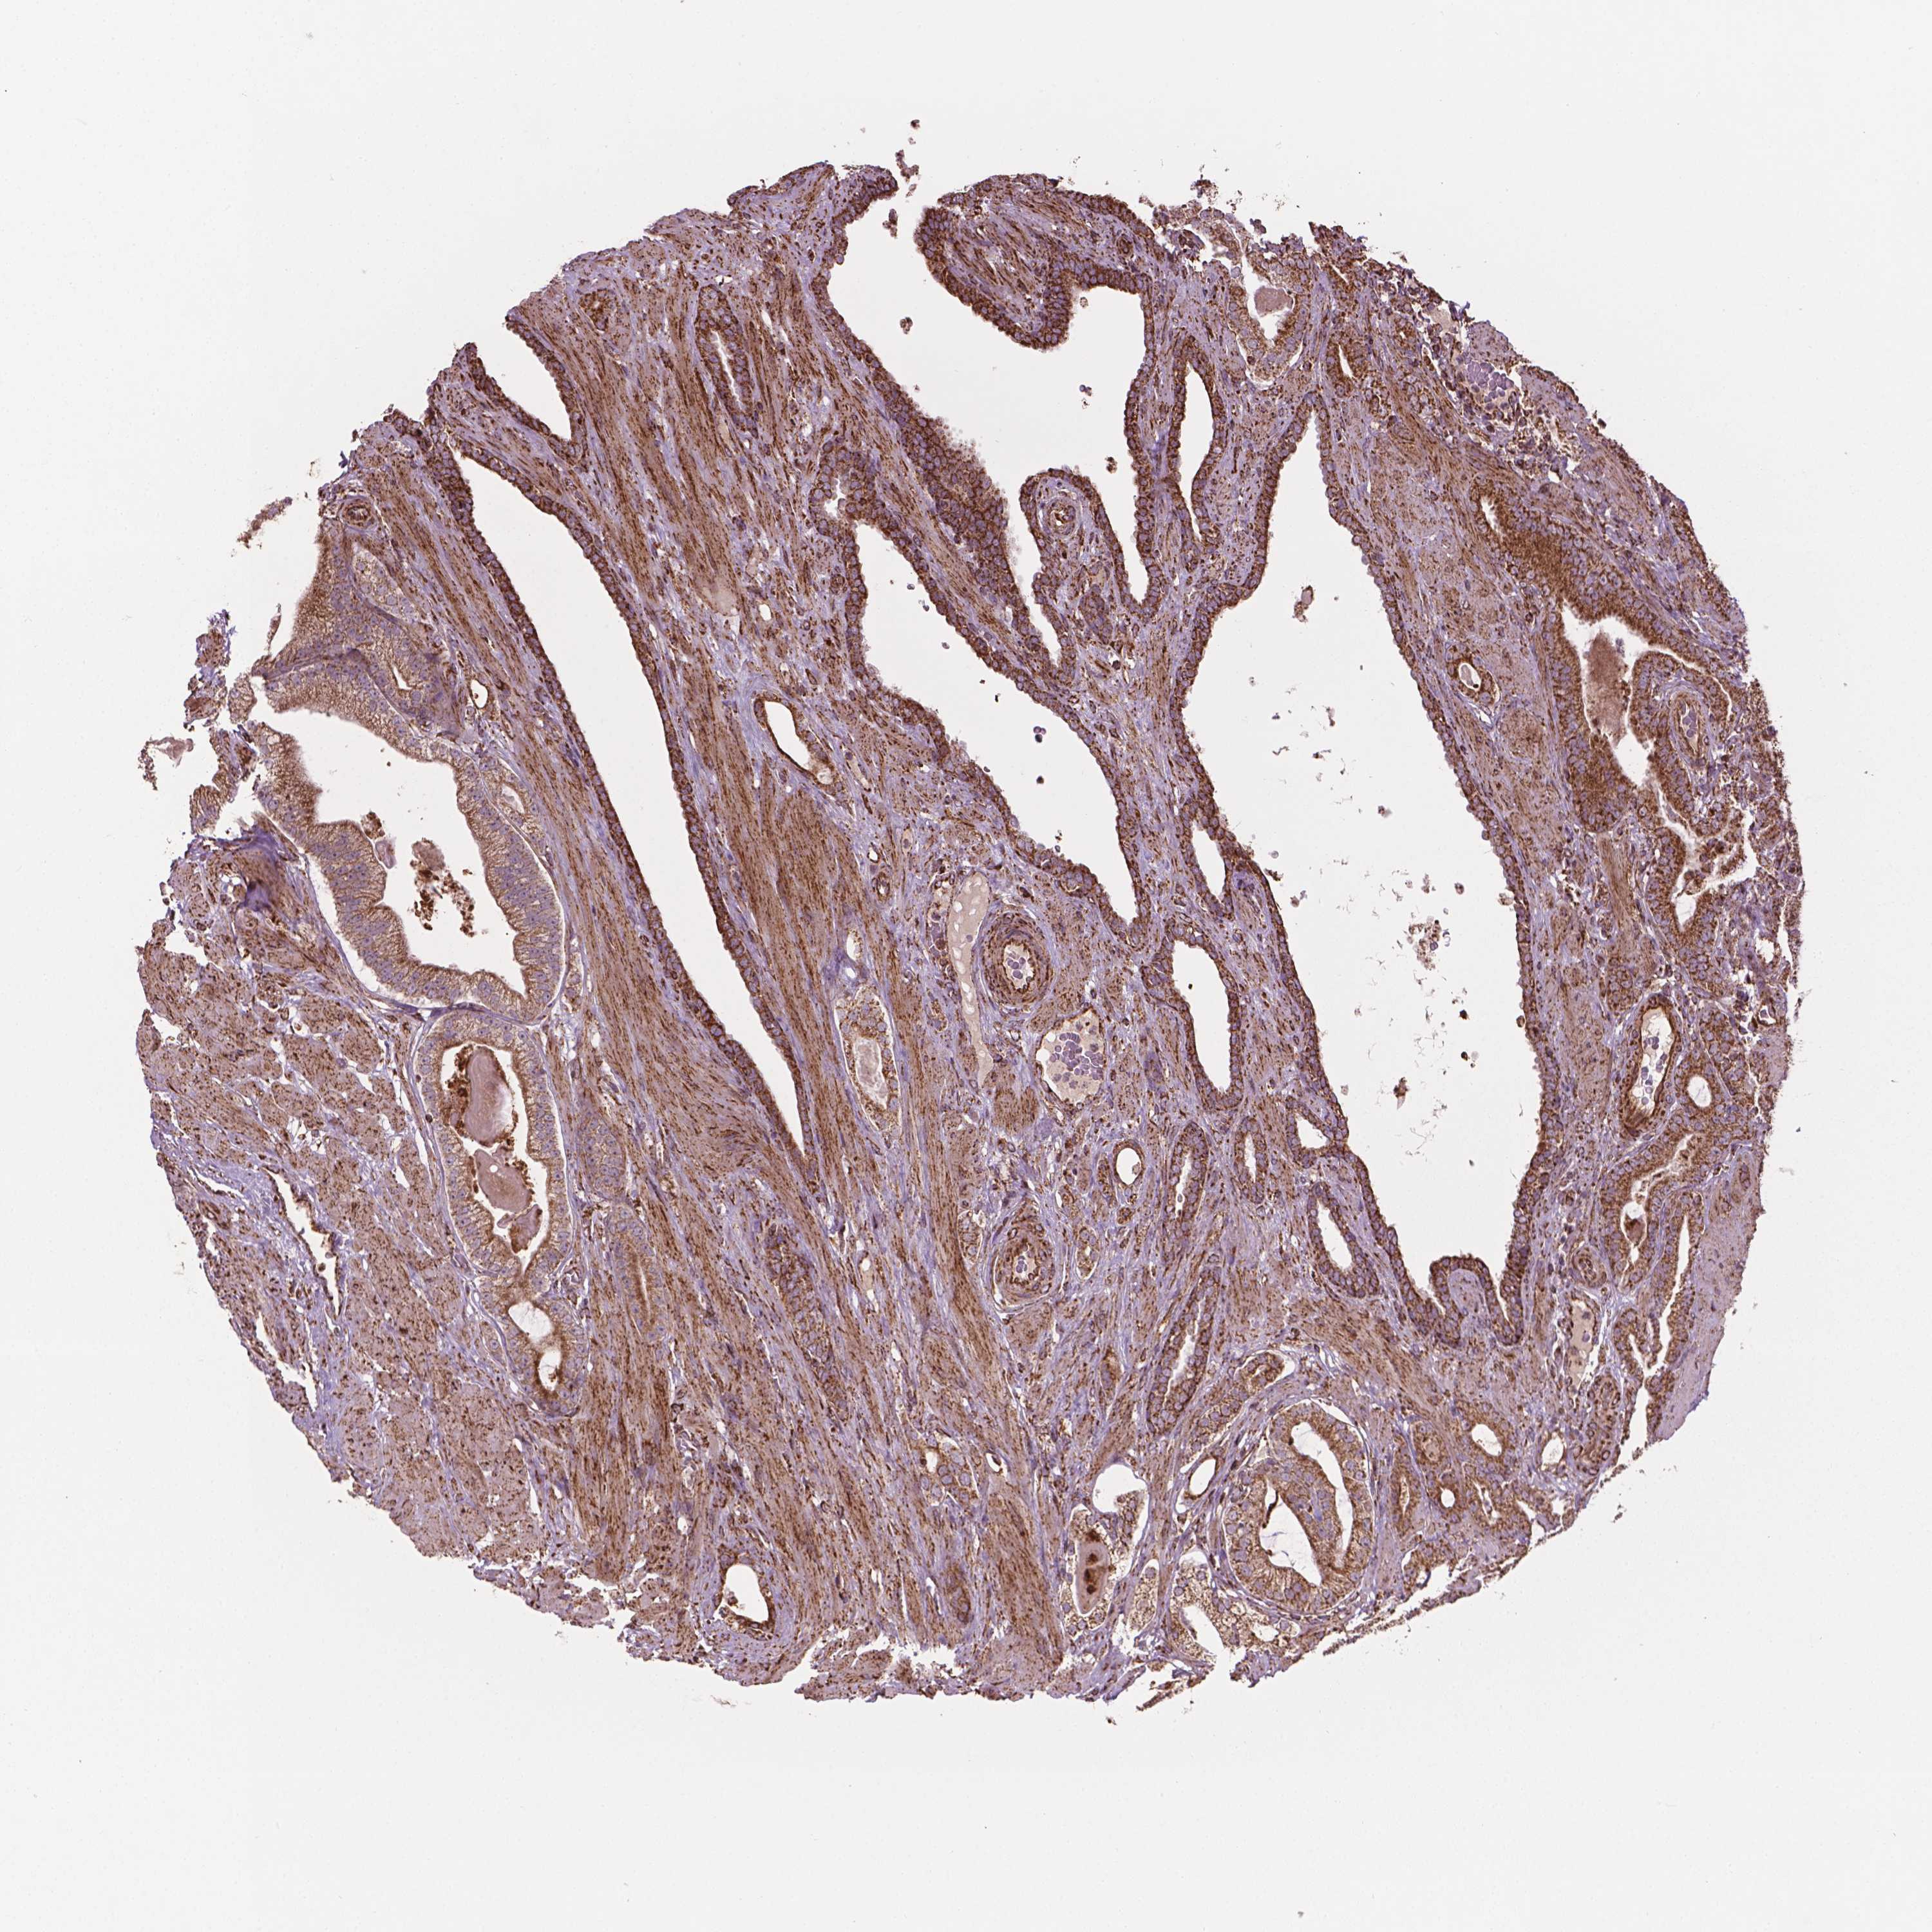

PROSTATE CANCER - Protein expressioni

A mouse-over function shows sample information and annotation data. Click on an image to view it in a full screen mode. Samples can be filtered based on level of antibody staining by selecting one or several of the following categories: high, medium, low and not detected. The assay and annotation is described here.

Antibody stainingi

Antibody staining in the annotated cell types in the current human tissue is reported as not detected, low, medium, or high, based on conventional immunohistochemistry profiling in selected tissues. This score is based on the combination of the staining intensity and fraction of stained cells.

Each image is clickable and will lead to virtual microscopy that enables deeper exploration of all samples and also displays staining intensity scores, fraction scores and subcellular localization as well as patient and tissue information for each sample.

Antibody HPA071530

Staining

High

Medium

Low

Not detected

Intensity

Strong

Moderate

Weak

Negative

Quantity

>75%

75%-25%

<25%

None

Location

Nuclear

Cytoplasmic/membranous

Cytoplasmic/membranous,nuclear

Adenocarcinoma, High grade

Adenocarcinoma, NOS

Adenocarcinoma, Low grade